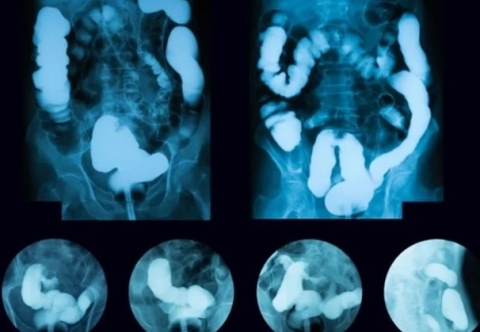

U mô đệm đường tiêu hóa (GIST) thường không gây ra triệu chứng rõ ràng ở giai đoạn đầu, vì vậy, việc phát hiện sớm có thể gặp nhiều khó khăn. Tuy nhiên, việc nhận biết những triệu chứng ban đầu có thể giúp phát hiện bệnh trước khi khối u phát triển lớn hoặc lan rộng, từ đó tăng khả năng điều trị thành công. GIST thường xuất hiện ở dạ dày hoặc ruột non, và các triệu chứng ban đầu có thể liên quan đến vị trí của khối u trong đường tiêu hóa.